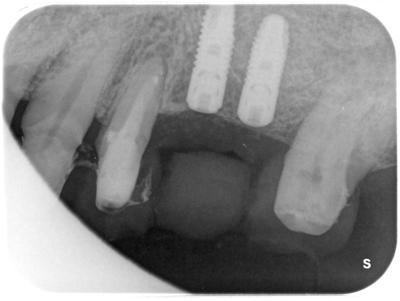

HOME > ブログ 一覧 > 左上56部へのサイナスリフトを伴うインプラント治療 2020.01.28左上56部へのサイナスリフトを伴うインプラント治療 左上56部2本欠損部へのインプラント。 術前写真。 術前CT。 インプラント治療行うには全く骨が不足している。 ラテラル法によるサイナスリフトを行い、インプラントを同時埋入。 使用インプラントはアストラEV。 間隔が狭いため、細めのインプラント2本で対応した。 術後。 骨が移植されているのが分かる。 複雑、難症例は当院の得意とするところです。 Recent Entries アライナー矯正(インビザライン、シュアスマイル)費用を2023年 1月から改訂させていただきます(01/09) 本年もよろしくお願いいたします(01/02) 年始の診療について(01/01) 新しいWEBへ移行、年末年始の診療のお知らせ(12/29) ダラダラ根管治療行っても治らないという事(12/21) Category その他の治療(126) インビザライン・矯正(52) インプラント治療(216) ホワイトニング(47) メインテナンス(21) 包括診療(95) 医院からのお知らせ(249) 審美治療(128) 日々雑感(283) 根管治療(100) 歯周病治療(90) 矯正(73) 補綴治療(45) 補綴治療カテゴリを追加(1) 診療全般(44) Archive 2023年1月(3) 2022年12月(6) 2022年11月(14) 2022年10月(6) 2022年9月(8) 2022年8月(7) 2022年7月(13) 2022年6月(8) 2022年5月(7) 2022年4月(7) 2022年3月(6) 2022年2月(7)